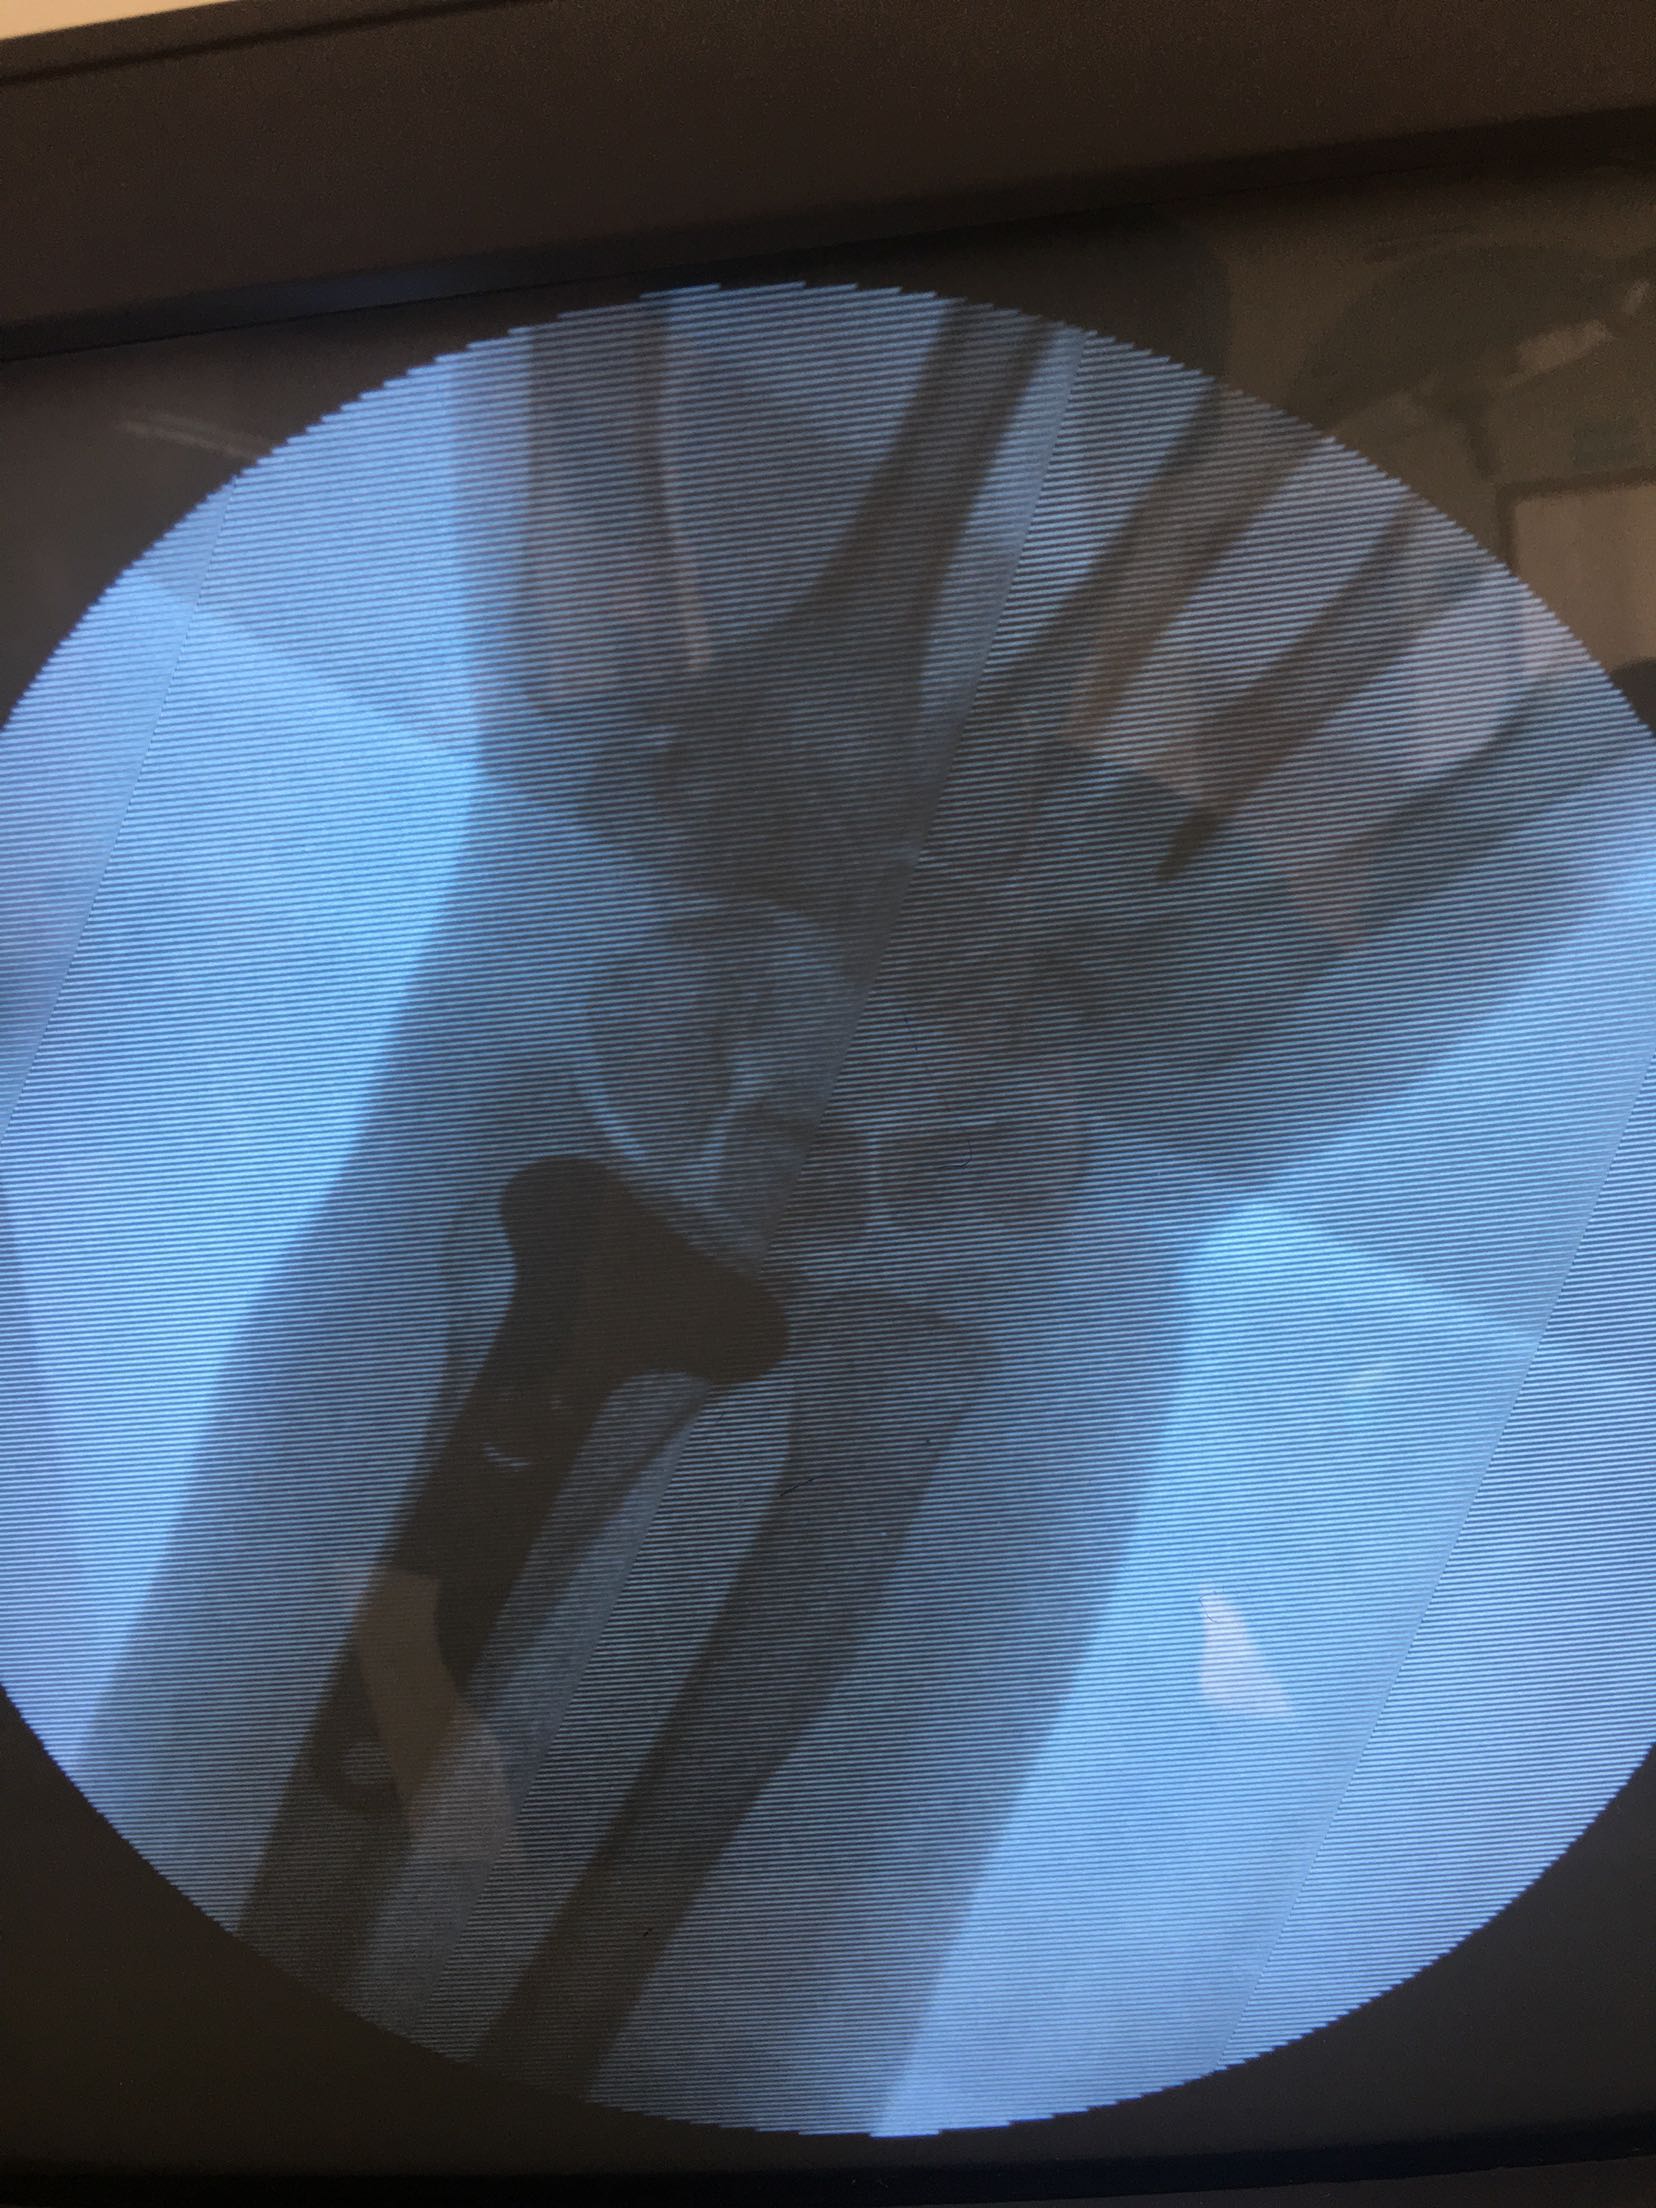

在臂丛麻醉下行切复内固定术,术后抗炎,消肿对症处理。